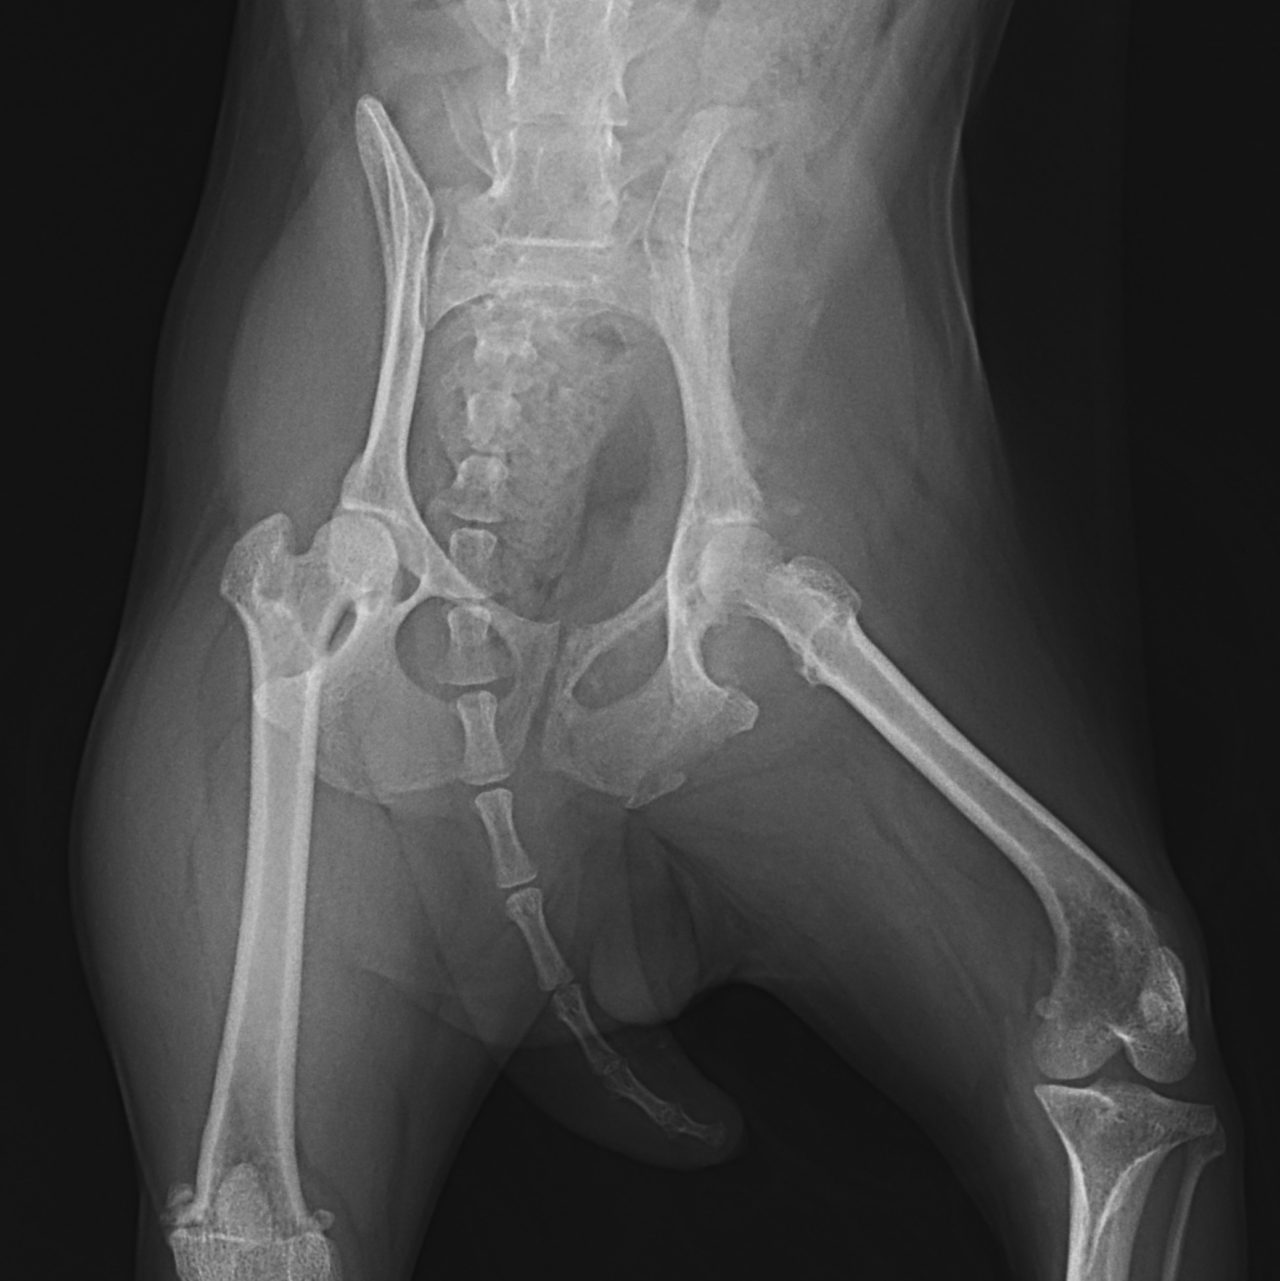

鎮痛剤で跛行が改善しないワンコの精査依頼がありました。CTでは股関節(主に腸骨)に骨融解像が確認されました。細胞診では悪性腫瘍と暫定診断が行われました。除痛のため半側骨盤切除で対応しました。後肢を失うことは大変辛いことですが、ワンコは痛みがなくなり快適に過ごせているそうです。一見、整形外科に見えても高齢犬には腫瘍が隠れていることがあるのでCTによる精査は大変有効です。